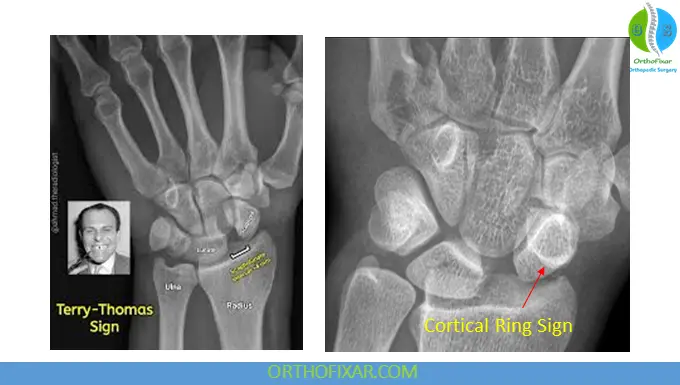

1. Terry Thomas Sign

- Widened scapholunate gap >3 mm (normal <2 mm)

2. Cortical Ring Sign

- Due to flexed scaphoid, creating a circular cortical appearance